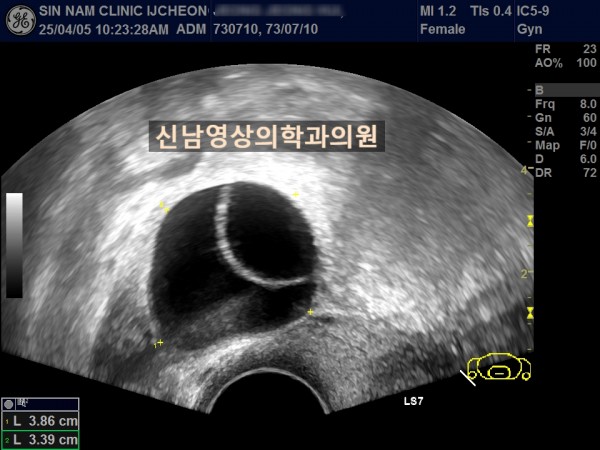

연령 : 52세

하복부 통증으로 내원하셨고, 초음파 검사상 자궁선근종과 난소낭종이 발견되었고, 난소암 혈액검사를 진행했습니다.

난소암 혈액검사 결과는 정상범위로 약간 높은 수치였기에 생리 끝나고, 다시 추적검사를 진행하기로 했지만 복통이 심해져 수술 진행했고, 수술장에서는 암의 가능성이 없는 것으로 전달 받았으나 최종 조직검사상 난소암으로 진단되었습니다.

여성들의 경우 난소 내막종에서 난소암으로 진행될 위험이 있고, 자궁선근종이 있는 분들은 난소내막종이 동반될 가능성도 높기 때문에 주기적으로 추적검사가 필요하고, 난소암 혈액검사와 초음파상 혹의 모양을 종합적으로 판단해 수술결정을 하게 됩니다.